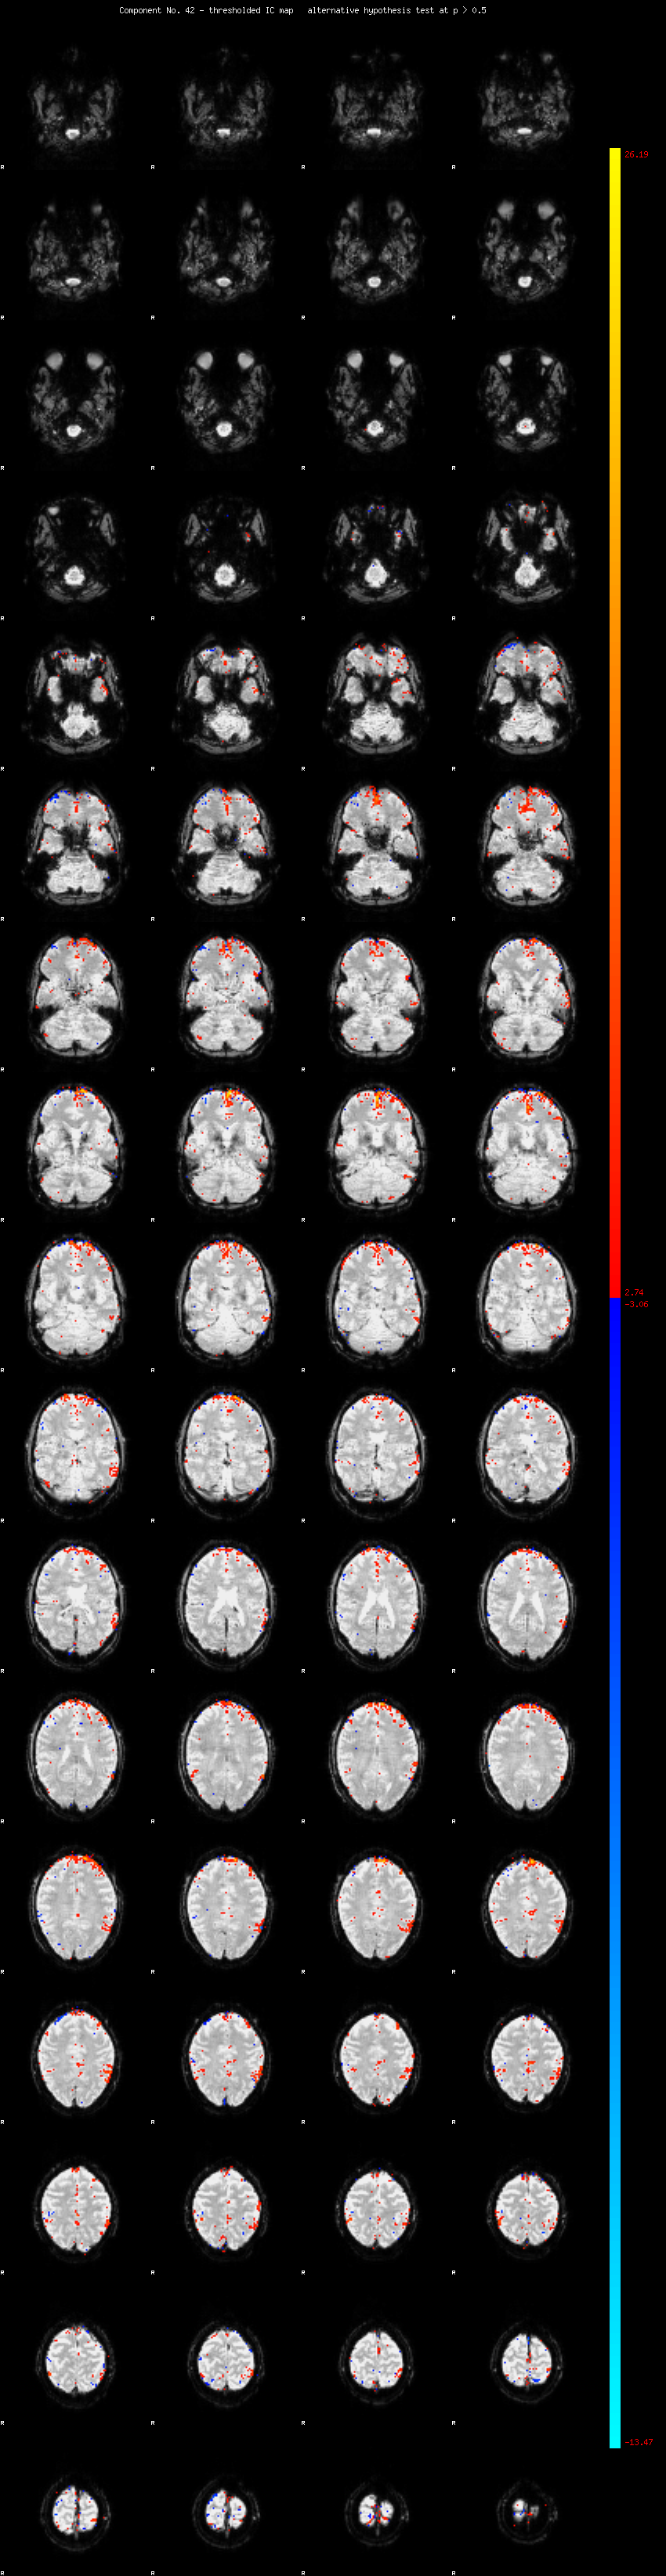

MELODIC Component 42

1.09 % of explained variance;     0.72 % of total variance